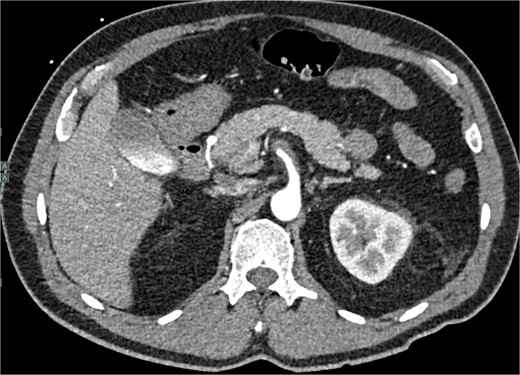

A 60-year-old male with a past medical history of hypertension presented to our emergency department with 45 minutes of severe abdominal pain accompanied by nausea and vomiting. The patient’s presenting blood pressure was 192/130 mmHg with a heart rate of 77 bpm, and the remaining vitals were within normal limits. On physical examination, tenderness was noted in the epigastric region without peritoneal signs. A CT of the abdomen and pelvis revealed a partial thrombosis of the SMA, extending into some of the mesenteric branch arteries, with no evidence of bowel ischemia. The patient was started on a high-dose heparin drip. A same-day repeat CT angiogram further indicated 75% SMA stenosis secondary to SMA dissection with thrombosis of the false lumen (Fig. 1).

CTA abdomen and pelvis demonstrating 75% SMA stenosis secondary to SMA dissection with thrombosis of the false lumen.